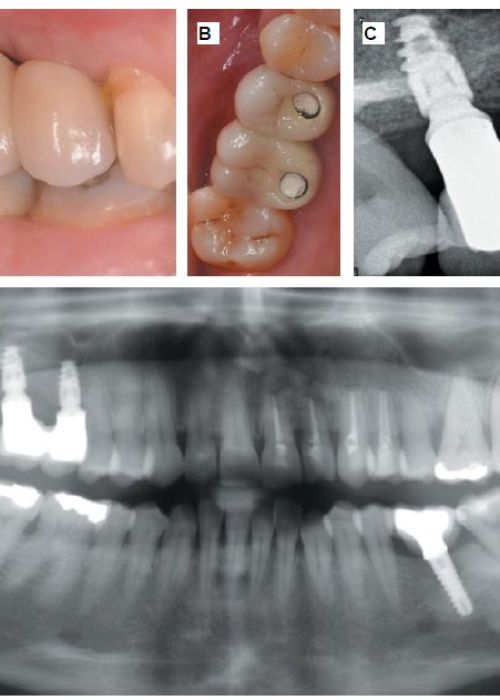

Comportamiento clínico, radiográfico e histomorfométrico del diente autólogo como biomaterial en elevación de seno maxilar de acceso lateral. Caso clínico con seis meses de seguimiento post-carga protésica

Clinical, radiographic and histomorphometric behaviour of the autologous tooth as a biomaterial in lateral access maxillary sinus elevation. Case report with six months of post-prosthetic loading follow-up